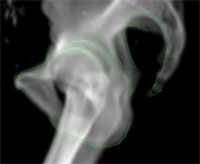

Besonders wichtig ist zunächst die genaue Lokalisation dieses Tumors, der benachbarte Organe nicht infiltriert, sondern bedrängt. Dazu muss zusätzlich zum Planungs-CT ein hochauflösendes MRT (Magnetresonanz-Tomogramm) angefertigt werden. Im MRT sind der Befund und der benachbarte Hirnstamm sehr gut erkennbar, im Planungs-CT dagegen nur schwer (Bild 1). MRT und CT werden in der Planungs-Software geometrisch zusammengeführt, man spricht von dem Prozess der „Bildregistrierung“. Nun kann der Arzt den Befund exakt im MRT konturieren und der Physiker die Berechnung und Optimierung der Dosisverteilung im CT vornehmen (Bild 2).

Bild 1: Links der Befund im Planungs-CT, rechts die gleiche Darstellung im 3D-MRT. Nur im MRT sind Tumor und Hirnstamm klar abgrenzbar. Es ist erkennbar, wie der Hirnstamm bereits bedrängt wird.